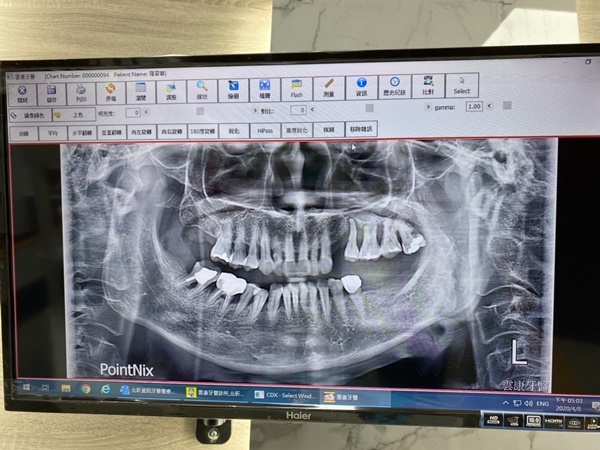

植牙醫師做微創植牙前要求非常仔細

會安排拍攝口腔斷層掃描由片子來解釋臼齒牙床健康情形

骨頭密度適不適合做微創植牙

要不是經由精密檢查真的很難知道原來自己牙槽骨頭好不好

一直到第四個月回診拍攝X光片植牙醫師確認牙床恢復不錯